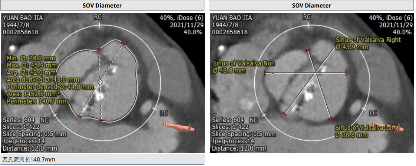

主动脉CT

该患者主动脉瓣为Type 0型二叶瓣,瓣叶中度钙化,钙化分布不均匀,主要分布左瓣,瓣环周长76.1mm,平均直径23.9mm;LVOT周长81.1mm,平均径25.0mm;钙化延伸至流出道10.5mm。左窦位置瓦氏窦瘤样膨出。瓣上6mm/8mm预估可推开空间周长70.7mm/67.5mm。左冠高度14.5mm,右冠高度18.3mm。

路径方面:两侧股动脉稍有迂曲,分叉高度可。左侧股动脉最小内径7.7mm,右侧股动脉最小内径7.0mm。